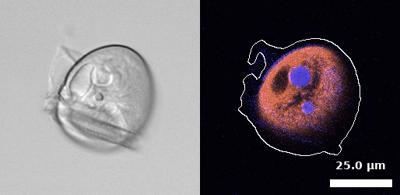

TissueGnostics is a solution provider for Precision Medicine and Next-Generation Digital Pathology. The company offers fully integrated microscopy platforms with support for a variety of applications in human, animal and plant tissue, as well as image analysis solutions using AI and machine-learning. Since AI was a topic that Annesha wanted to work on for her Master’s thesis project, she approached TissueGnostics with the possibility of a master’s thesis project along with the internship.

“My internship project focuses on establishing a framework to compare different segmentation algorithms in histopathology,” explains Annesha. “But I have interactions with everyone in the office. I have been exposed to so much, including production and even marketing. It’s been really eye-opening.”